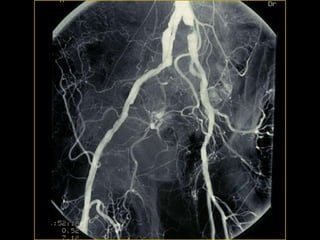

Arteriography

Digital subtraction

1- Laboratory investigations: 2-Imaging: - Doppler flow study. • ABI • Segmental pressure - Duplex scanning - Arteriography Arteriography